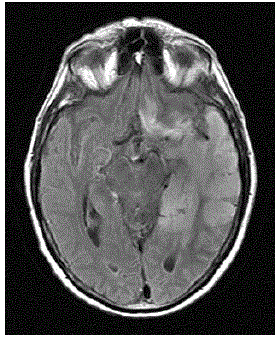

Mulher de 60 anos de idade refere dor epigástrica, tosse e náuseas após as refeições há cerca de 1 ano. Realizou uma radiografia de tórax com a imagem abaixo:

Qual é o diagnóstico mais provável?